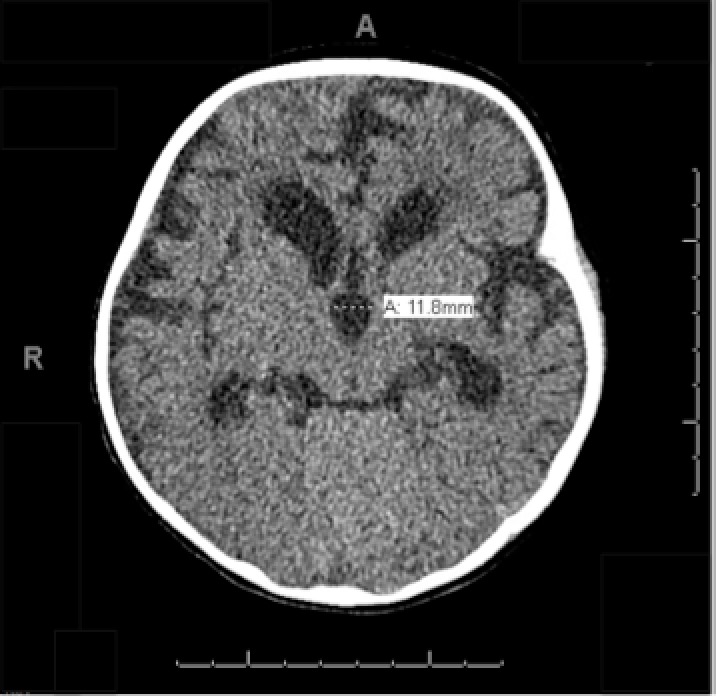

03/15/2023

An 11-year-old boy with a medical history significant for autism spectrum disorder and attention-deficit/hyperactivity disorder presented to the emergency department with a 1-month history of progressive...